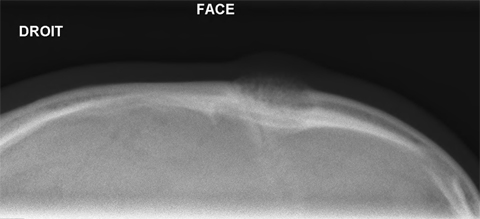

Cas clinique N°53

Dr Véra Lemaire Paris

Il s'agit d'un homme de 39 ans, sans antécédents particuliers, qui consulte pour une tuméfaction frontale gauche augmentant progressivement depuis 6 mois.

La tuméfaction est dure, indolore, sans signes inflammatoires.

Radiographie centrée sur la lésion.

Quel(s) examen(s) demandez-vous ?

Quel diagnostic proposez-vous ?